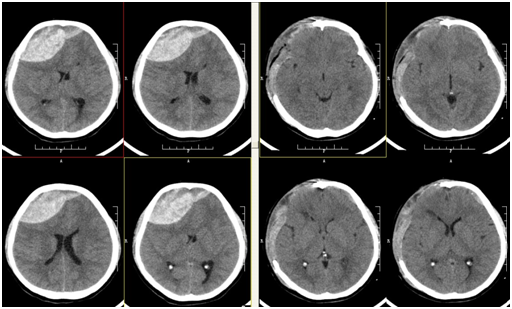

患者郭某某,女,23岁,因“头痛进行性加重7小时,加重呕吐、意识障碍2小时”于2016-04-04入院。病例特点:1、青年患者,急性发病。2、病例特点:患者家属代诉于7小时前无明显原因出现头痛,到当地医院就诊,查头颅CT提示:右侧额部硬膜外血肿,2小时前开始出现呕吐,并有意识障碍,瞳孔散大,家属为进一步求治,转诊我院求治。复查头颅CT提示:脑疝、双侧额部硬膜外血肿(以右侧为主)、脑肿胀明显。拟“脑疝、双侧额部硬膜外血肿”收入院。入院查体:呼吸机辅助呼吸(呼吸微弱),昏迷,双侧瞳孔散大,右侧瞳孔6.0mm,左侧瞳孔4.5mm,对光反射消失。刺痛无反应。

2016年4月4日晚上急诊全麻下为患者行“双侧额部硬膜外合并硬的膜下血肿清除术+去骨瓣减压术”,术程顺利,术中颅压高,考虑术前患者已经出现脑疝,术中给予去除右侧额颞部骨瓣缓解颅内高压,皮下放置引流管,术后给予预防感染、脱水、支持、对症等综合治疗。术后第一天患者神志清楚,对答切题,四肢肌力5级,NS(-)。